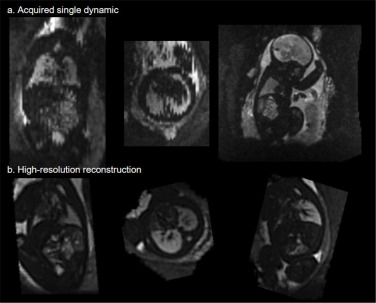

图1.低场下定量T2*胎儿身体MRI和分割的完整FOREST流程(从左到右)。图像采集后,图像经过去噪处理,使用卷积神经网络(CNN)分割胎儿身体,然后分割主要器官(肺、心脏、肝脏、腹部)以将胎儿身体重新定向到标准空间。接下来,对每个采集到的回波进行可变形切片到体素重建(dSVR),然后使用所有三个重建回波进行T2*拟合,并分割成十个胎儿身体器官。计算每个器官的平均T2*值并与胎龄(GA)进行比较。

图4.上排(a):重建前单个有运动伪影的动态图像示例。请注意左侧和中间图像中可见的切片之间的运动伪影;下排(b):同一病例在所有三个平面上重建后的3D体积,运动伪影已消除。